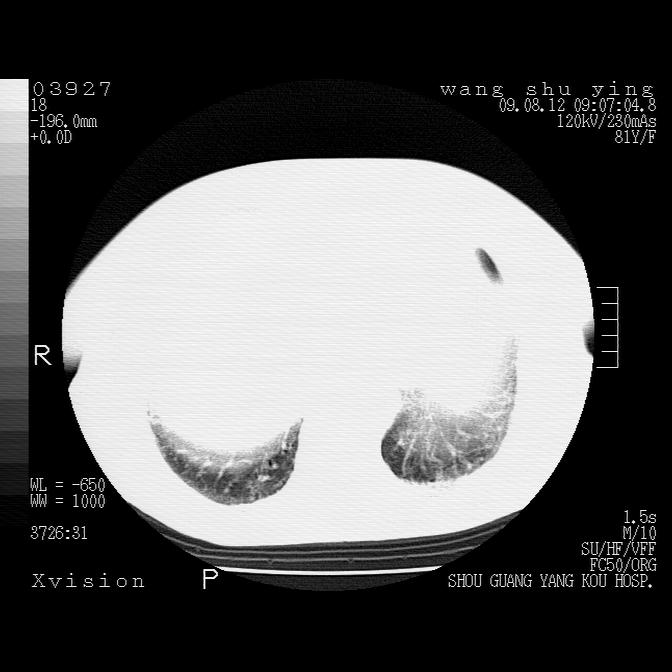

以下是引用帅河马在2009-8-12 12:59:00的发言:[br]两肺感染性病变伴双侧胸膜肥厚。[br]左侧甲状腺腺瘤不除外。[br]腹水+心包积液。[br][br][本贴已被 帅河马 于 2009-8-12 13:14:32 修改过]

以下是引用sdzyy在2009-8-12 18:17:00的发言:[br]两肺感染性病变伴双侧胸膜肥厚。[br]左侧甲状腺腺瘤不除外。[br]腹水+心包积液。[br]支持

以下是引用随光逐影在2009-8-12 19:42:00的发言:[br]1)两肺感染性病变伴双侧胸膜肥厚。2)不排除左侧甲状腺腺瘤。3)肝脏占位性病变;建议行进一步检查。